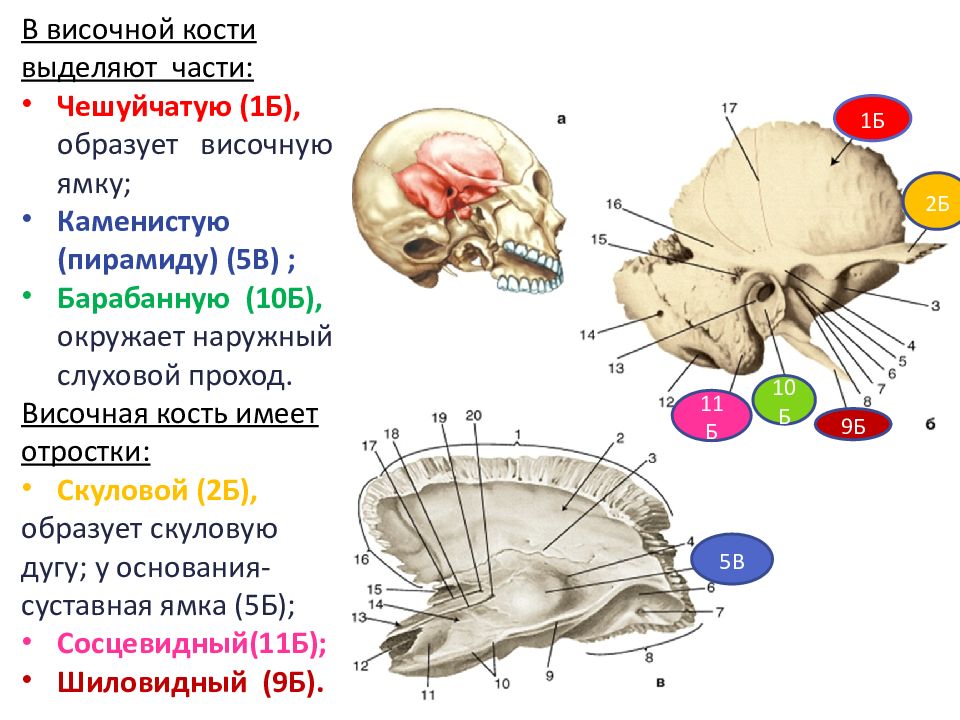

Анатомия и особенности фиссуры петротимпаника